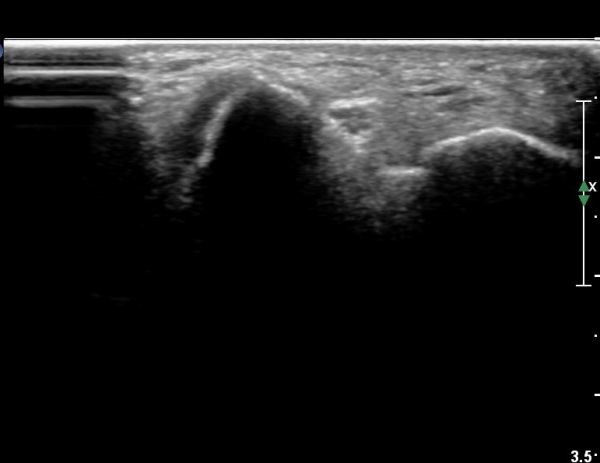

4 sono.jpg